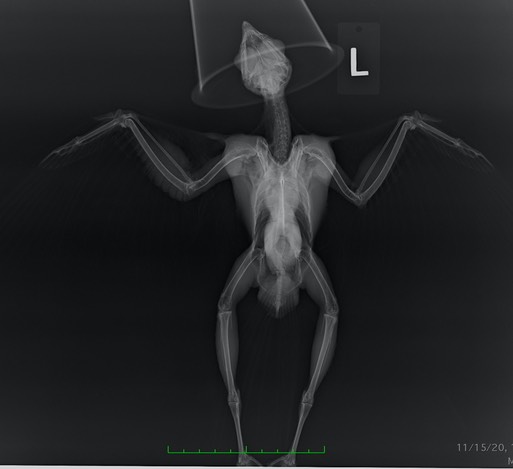

Great Horned Owl 20-580

The first admission this past week was an owl found along a road near La Grande, OR. It was presumed to have been hit by a car. An exam and radiograph found injuries consistent with being shot. The projectile was likely non-lead. It fractured the owl’s left clavicle, coracoid and ulna without fragmenting or leaving traces of metal. Non-lead projectiles are made of metals like copper or steel. They are harder than lead and do not deform or fragment when they strike bone. You can see from the radiograph below that the owl was very well muscled, indicating she was an accomplished hunter, likely catching and consuming multiple rodents per night. She was providing a great service to the agricultural community.